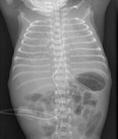

如結核病是由結核分枝桿菌引起的肉芽腫性炎,其病變特征是形成典型的結核性肉芽腫(tuberculous granuloma),即結核結節(tuberculous nodule),該結節的中央為干酪樣壞死,周圍伴有增生的上皮樣細胞和朗漢斯多核巨細胞(langhans multinucleate giant cell),并伴有淋巴細胞和成纖維細胞圍繞。

是指結節病時發生的非壞死性上皮樣細胞肉芽腫。結節病是一種尚未明確病因的全身性疾病。該肉芽腫主要由上皮樣細胞、多核巨細胞和淋巴細胞構成,無干酪樣壞死。